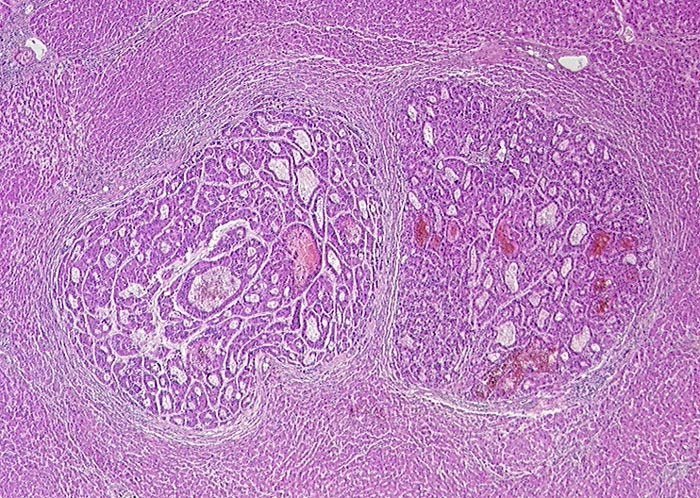

Hepatozelluläres Karzinom

Das Tumorgewebe in der Bildmitte ist diskret basophiler als das umgebende Leberparenchym. Leberzellähnliches Gewebe aus doppel- oder mehrreihigen Zellplatten. Diese bilden pseudoglanduläre Strukturen aus.

Zufallsbefund bei Autopsie: Metastasierendes Hepatozelluläres Karzinom mit Tumorperforation und 3000ml blutigem Aszites. Keine Leberzirrhose.